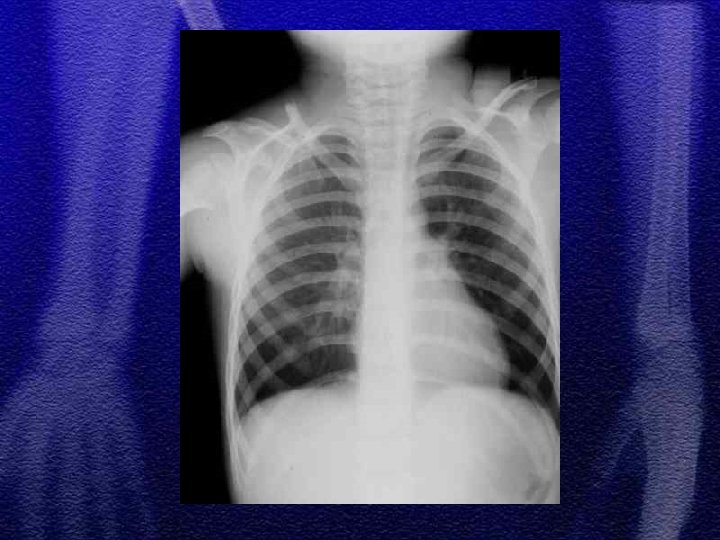

§ W obrębie powłok - zadrapania, wylewy krwawe, obrzęki w różnych stadiach gojenia, oparzenia, ubytki kępek włosów, naderwane uszy § złamania kości czaszki, żeber, kości długich w okolicach nasad i przynasad, związane z pociąganiem i skręcaniem kończyn - nawarstwienia okostnowe § złamania kompresyjne kręgosłupa mogą być wynikiem powtarzanego potrząsania dzieckiem

§ Najczęściej są to następstwa urazów okołoporodowych § złamania obojczyka - wystarczy 7 -10 dniowe unieruchomienie miękkiegojenie poprzez wytworzenie obfitego guza kostniny § złamanie trzonu kości udowej - wyciąg plastrowy pionowy, rozwórka Koszli 2 -3 tyg. § złamania kości ramiennej - miękki opatrunek Desaulta 2 tyg. § złuszczenia nasad występują sporadycznie